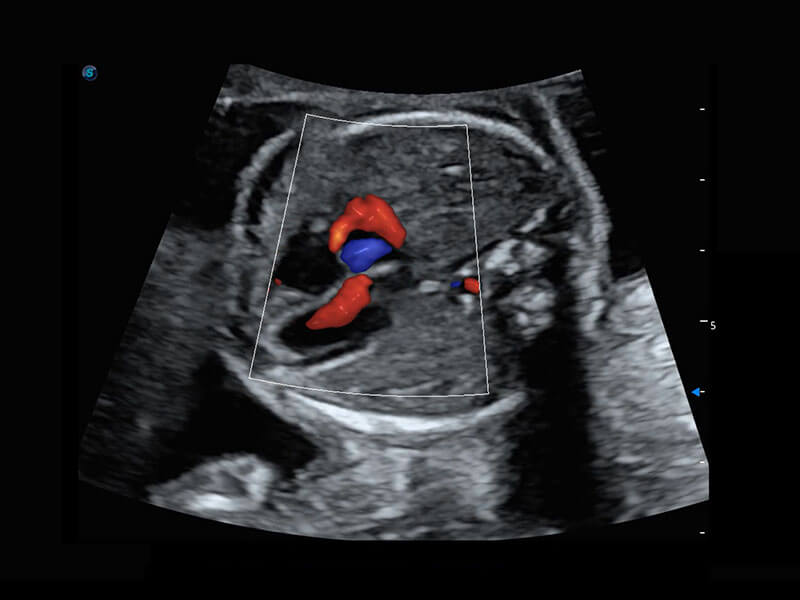

胎心筛查

P60搭载一系列胎儿心脏成像技术,实现精细的胎儿心脏评估。

• 四腔心血流

• 右室双出口